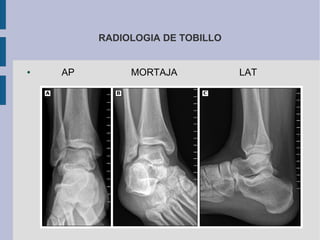

RADIOLOGIA DE TOBILLO

● AP MORTAJA LAT

● Rx es útil para lesiones agudas de tobillo y RMN no tiene

beneficio para esas lesiones.

● RMN esta indicado en lesiones de tobillo que no han

mejorado tras 6-8 semanas y que no mejoran el dolor.